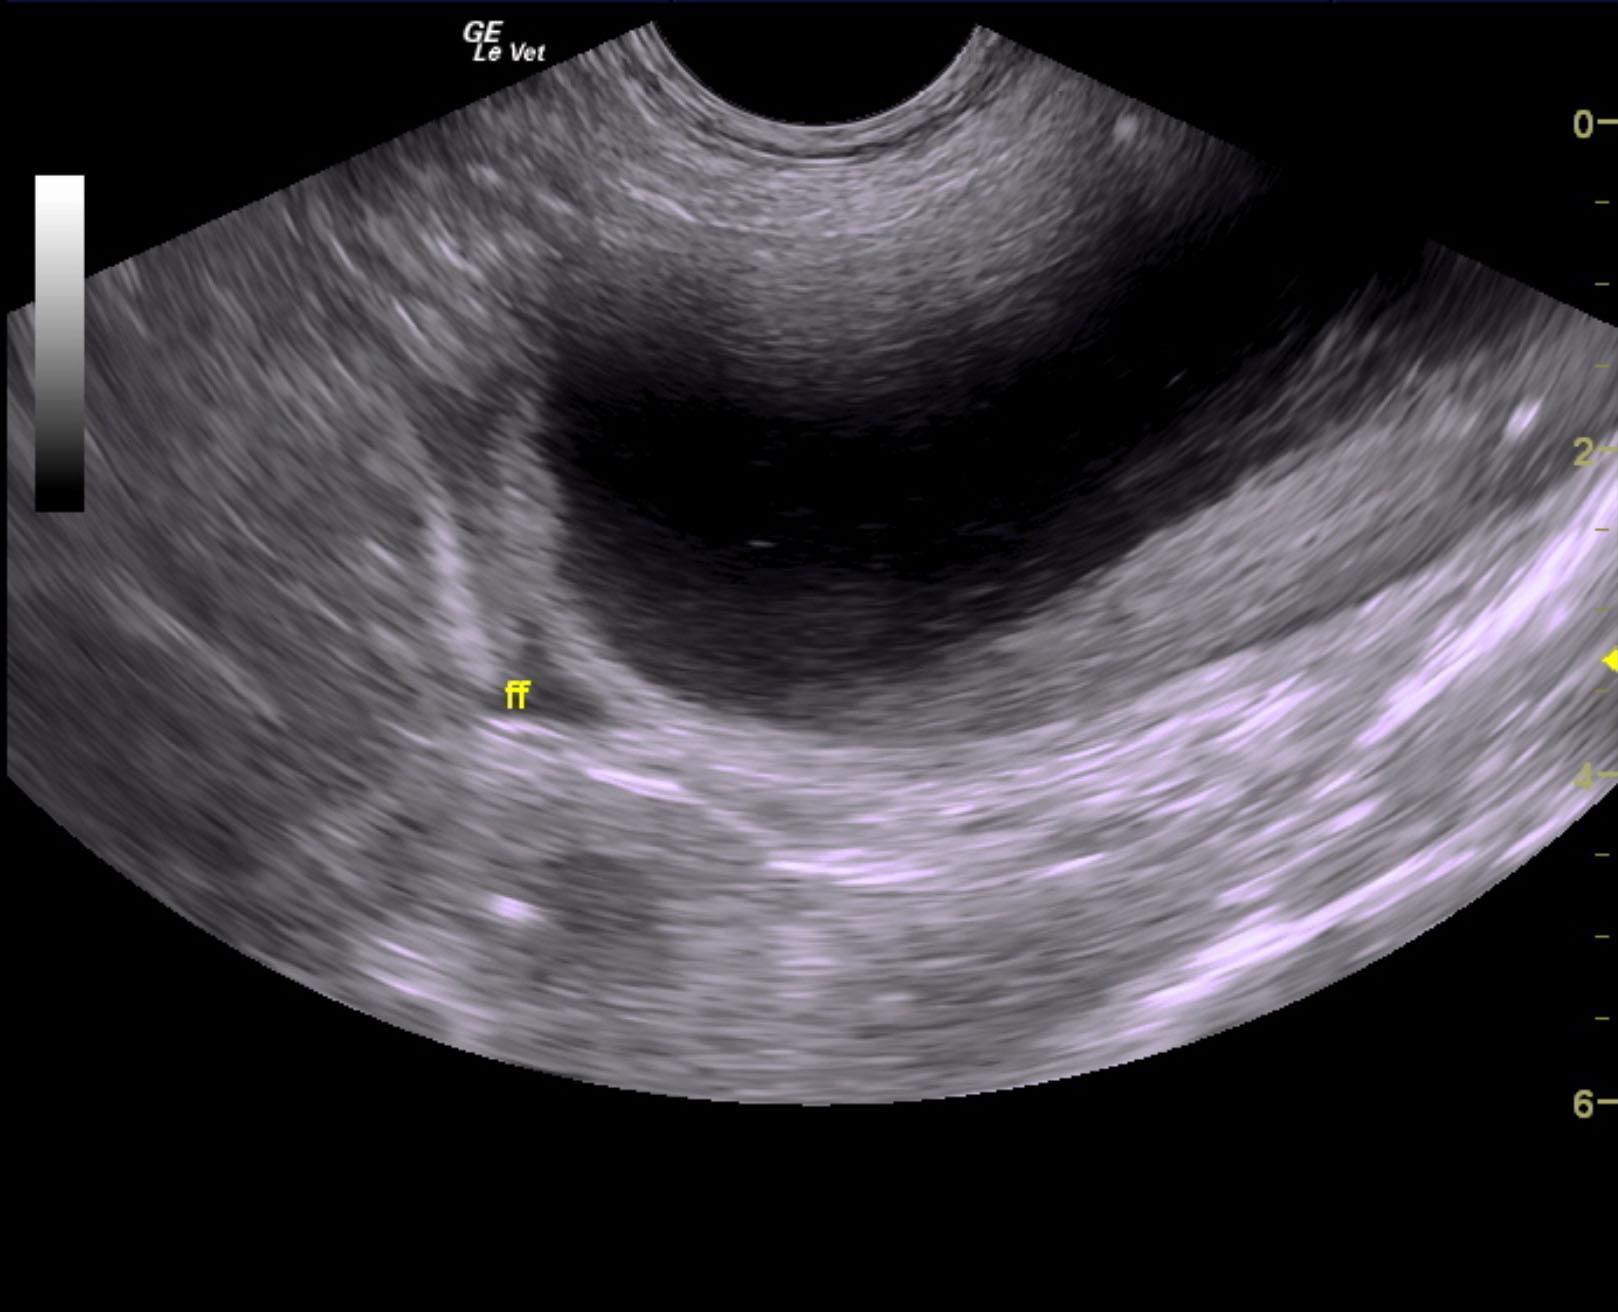

A 5-years-old male neutered Shih Tzu was presented for evaluation of urethral obstruction that had been managed with catheterization. Urinalysis showed SG of 1.008 and proteinuria. Abnormalities on CBC and serum biochemistry were neutrophilia and monocytosis, elevated phosphorus, and azotemia; the latter had improved after being catheterized.